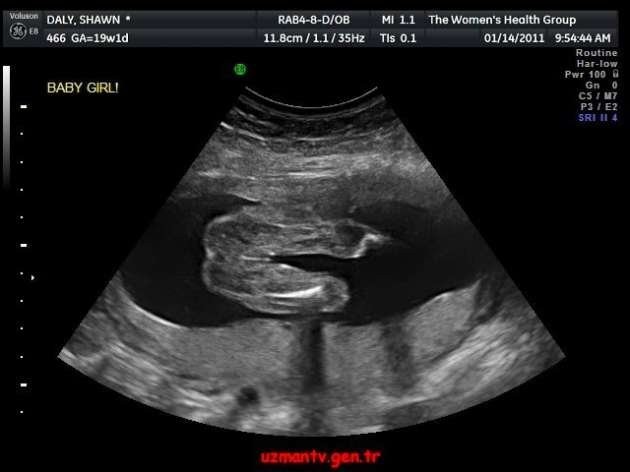

Bebeğinizin olacağını öğrendiğiniz ve büyük bir heyecanla doktorun yolunu tuttuğunuz o anı hayal etmeye çalışın. Şimdi de ultrasonda bebek yerine bir ördek gördüğünüzü düşünün. Merak etmeyin, aslında sadece “pareidolia” sendromunu yaşıyorsunuz. Yani gördüğünüz alelade şekilleri anlamlandırmaya çalışma hali… İşte bebek ultrasonlarında çekilen ve bazı anne babalara mini kalp krizi geçirten bebek fotoğrafları!